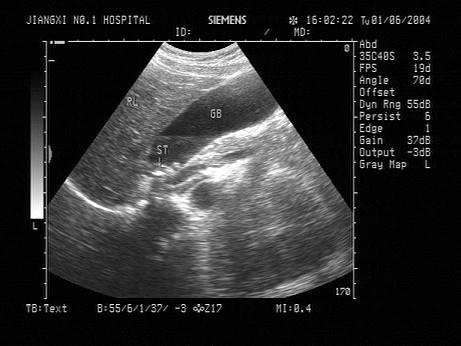

问题 女,35岁,上腹经常疼痛不适。声像图如图所示。结合超声声像图,诊断为?(?)

选项 A.胆囊多发性息肉 B.胆泥淤积 C.胆囊多发性腺瘤 D.胆囊蛔虫残骸 E.胆囊多发性结石

答案 E